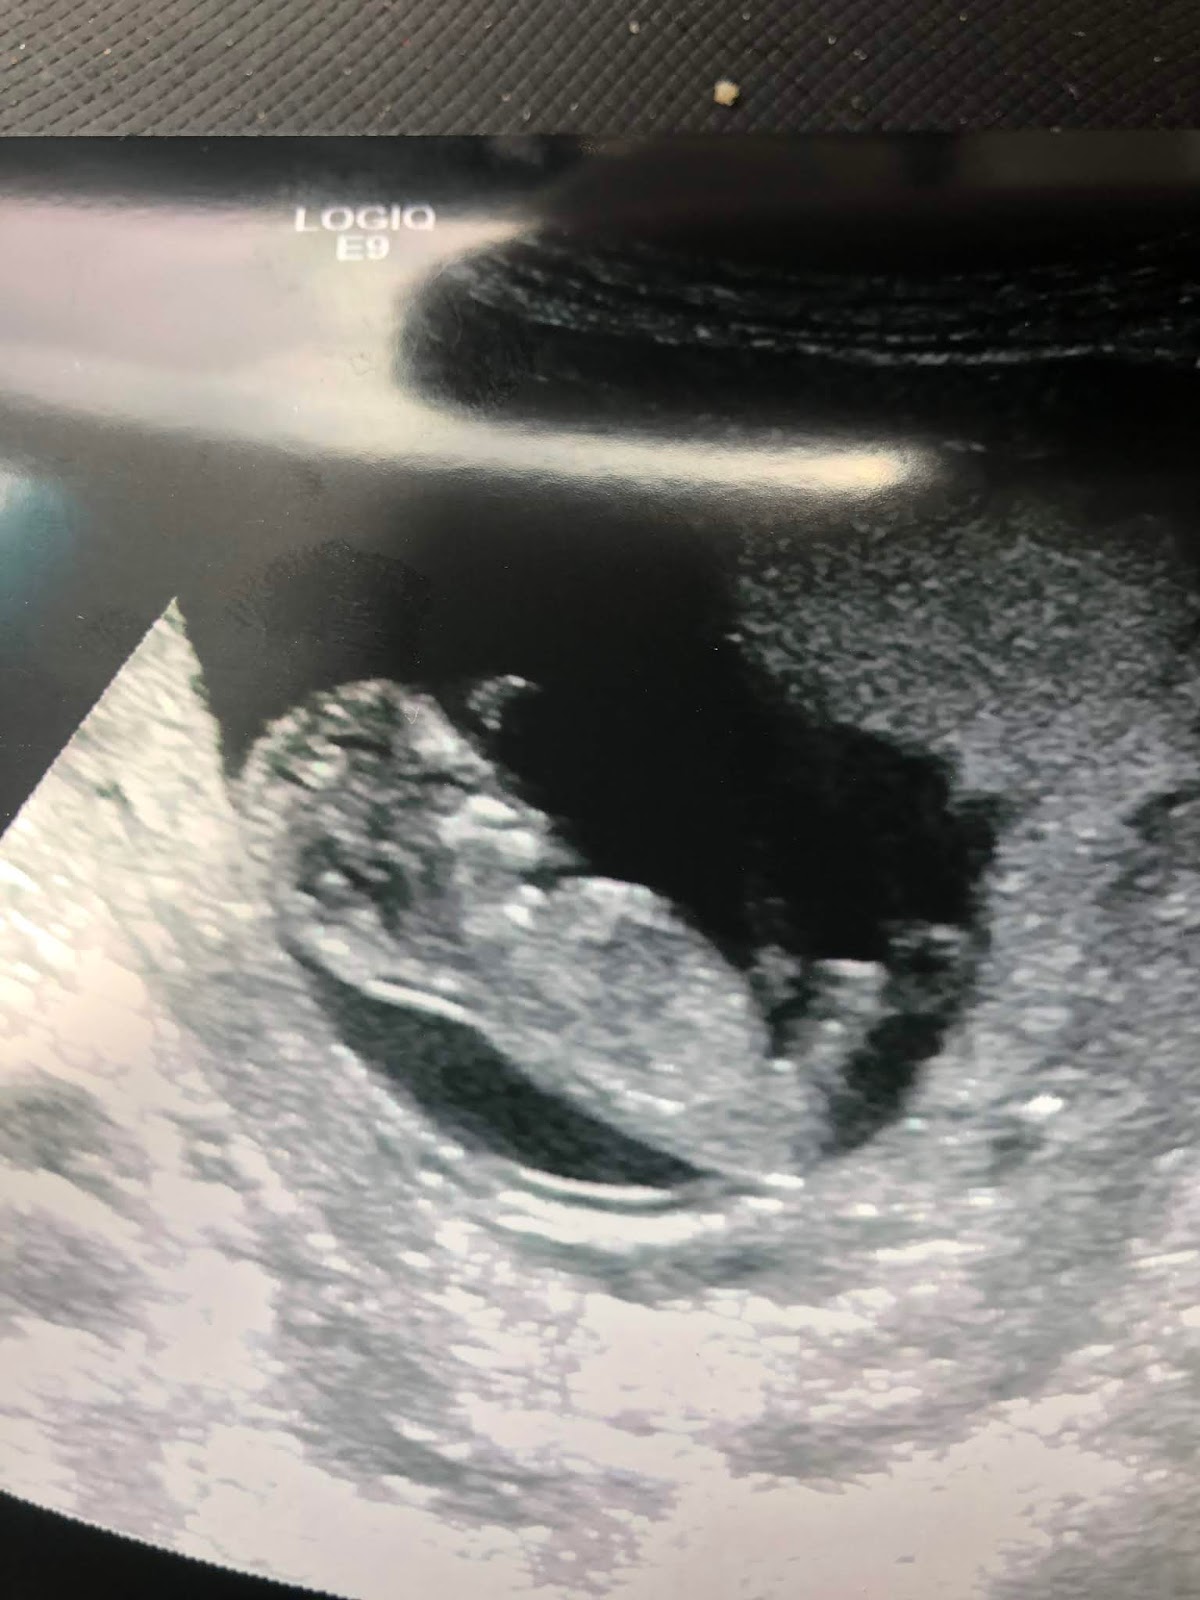

I 'met' our lovely baby in an ultrasound just days after the kids started school, but didn't know yet that she was a 'she'.

The technician and her co-op student asked about my other kids and their genders and they both winked at each other when they did my scan. I assume in hindsight that they had figured out I was carrying a girl and they quietly felt happy for me to not be quite so outnumbered anymore. And Anna, dear Anna, to have a sister among all those boys :)